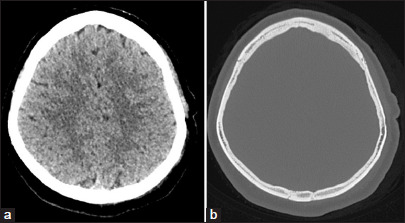

结缔组织增生纤维瘤(DF)是一种罕见的良性骨肿瘤,通常累及面部骨骼,累及颅脑极为罕见。我们报告一个独特的病例DF在一个28岁的妇女的顶骨,值得注意的是其在怀孕期间快速增长的现象,以前没有记录。该病例的影像学特征也与以往报道的所有病例不同。患者接受手术切除,组织病理学证实DF(胶原纤维瘤)的诊断。随访17个月,未见局部复发。我们也提供了32例涉及颅脑DF的病例,分析临床特征、影像学表现、治疗方法和复发模式。本病例强调了在颅脑病变鉴别诊断中考虑DF的重要性,特别是在肿瘤快速生长的孕妇中。为了减少复发的风险,广泛的手术切除仍然是推荐的治疗方法。

Desmoplastic fibroma (DF) is an uncommon benign bone tumor that typically affects the facial bones, with cerebral cranium involvement being extremely rare. We report a unique case of DF in the parietal bone of a 28-year-old woman, notable for its rapid growth during pregnancy-a phenomenon not previously documented. The imaging features of this case also differ from all but one previously reported case. The patient underwent surgical removal, and histopathology confirmed the diagnosis of DF (collagenous fibroma). After 17 months of follow-up, no local recurrence was observed. We also provide a comprehensive review of 32 cases involving DF of the cerebral cranium, analyzing clinical features, imaging findings, treatment methods, and recurrence patterns. This case highlights the importance of considering DF in the differential diagnosis of cranial lesions, particularly in pregnant patients with rapid tumor growth. Complete surgical resection with a wide margin remains the recommended treatment to minimize recurrence risk.